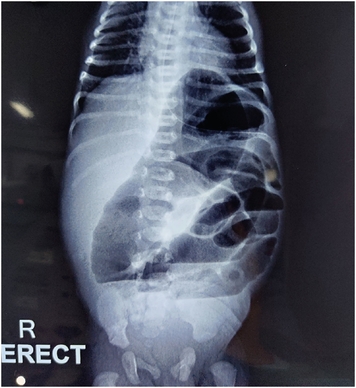

The excised specimen (Fig. 3) on histopathology examination was reported as a dysplastic proximally atretic ileum and a tubular duplication cyst in the fleshy structure fished out from the distal end. Post operative course was uneventful (Fig. 4). Patient was kept nil per oral for 5 days, gradually weaned to full feeds and discharged by 9th post operative day. On follow up visit he was doing well.

Fig. 3

Complete resected specimen of proximal (dilated) and distal atretic bowel with the fleshy structure.

On exploration via right upper quadrant transverse incision, a dilated, blind ending ileum with a wide mesenteric defect was noted at about 120 cm distal to Duodeno-jejunal flexure. The proximal ileum and jejunum were rotated 1.5 turns clockwise about their mesentery with maintained bowel viability. On de-rotation the mesentery was narrow and Ladd’s bands were also noted. Duodeno-Jejunal flexure was at its normal position. Ladd’s bands were divided and primary resection and anastomosis was planned. On incising the blind end of the distal ileum, a tubular structure of about 3 cm was extracted from its lumen (Fig. 2). This fleshy tube had no luminal communication with the distal bowel and its distal most part appeared blackish and necrotic. The dilated proximal atretic bowel about 15 cm & the tubular 3 cm structure along with a portion of distal ileum was excised and end to end anastomosis performed.

Fig. 2

Distal atretic bowel (bowel lip grasped with forceps) from whose lumen a thin fleshy tube-like structure (duplicated intussuscepted bowel) with blackish necrotic distal end was pulled out.